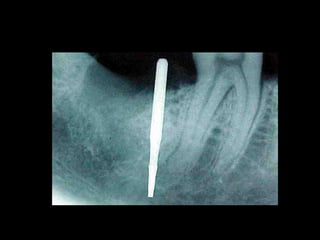

Rx Intraoral: Técnica De Cono Largo

• Altura de hueso disponible

• Relación con estructuras

anatómicas

• Amplitud

• Relación con piezas vecinas

• Presencia de patologías y-o

cuerpos extraños

• Traveculado óseo

Rx Periapical

• Es el método más

importante para los

controles postoperatorios

Controlan

fundamentalmente:

Asentamiento y

Ajuste protético

Estabilidad ósea

periimplante

Altura de Hueso Disponible: Relación con

estructuras anatómicas nobles

Es la altura de hueso que va desde la cresta alveolar hasta

1,5 o 2 mm de las estructuras anatómicas a preservar